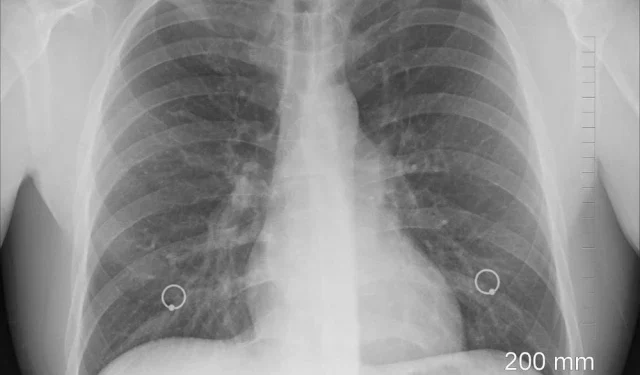

Some 100,000 people worldwide are estimated to suffer from cystic fibrosis, in which sticky mucus builds up in the lungs, digestive tract and other parts of the body.